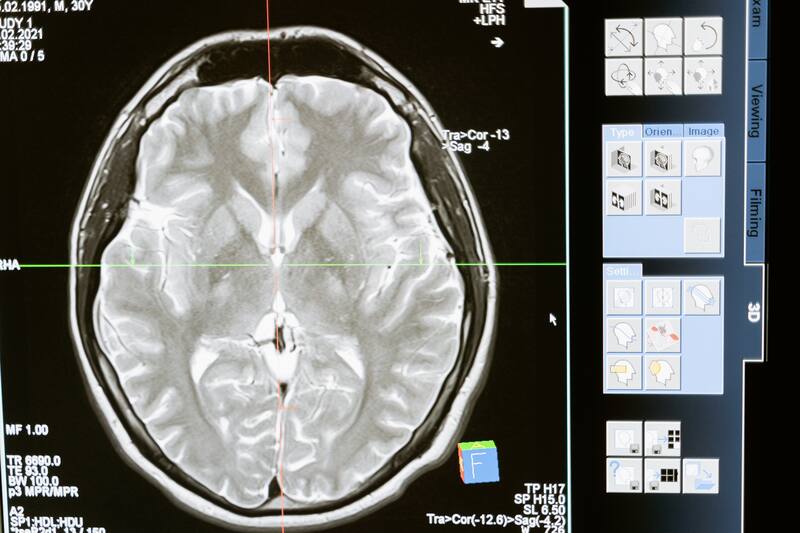

Después de examinar el genoma del colombiano, lograron identificar que tenía una mutación distinta que lo habría ayudado a protegerse contra la enfermedad. Además, con los escáneres cerebrales que realizaron, encontraron una región clave en su cerebro que también habría estado protegida del gen devastador.